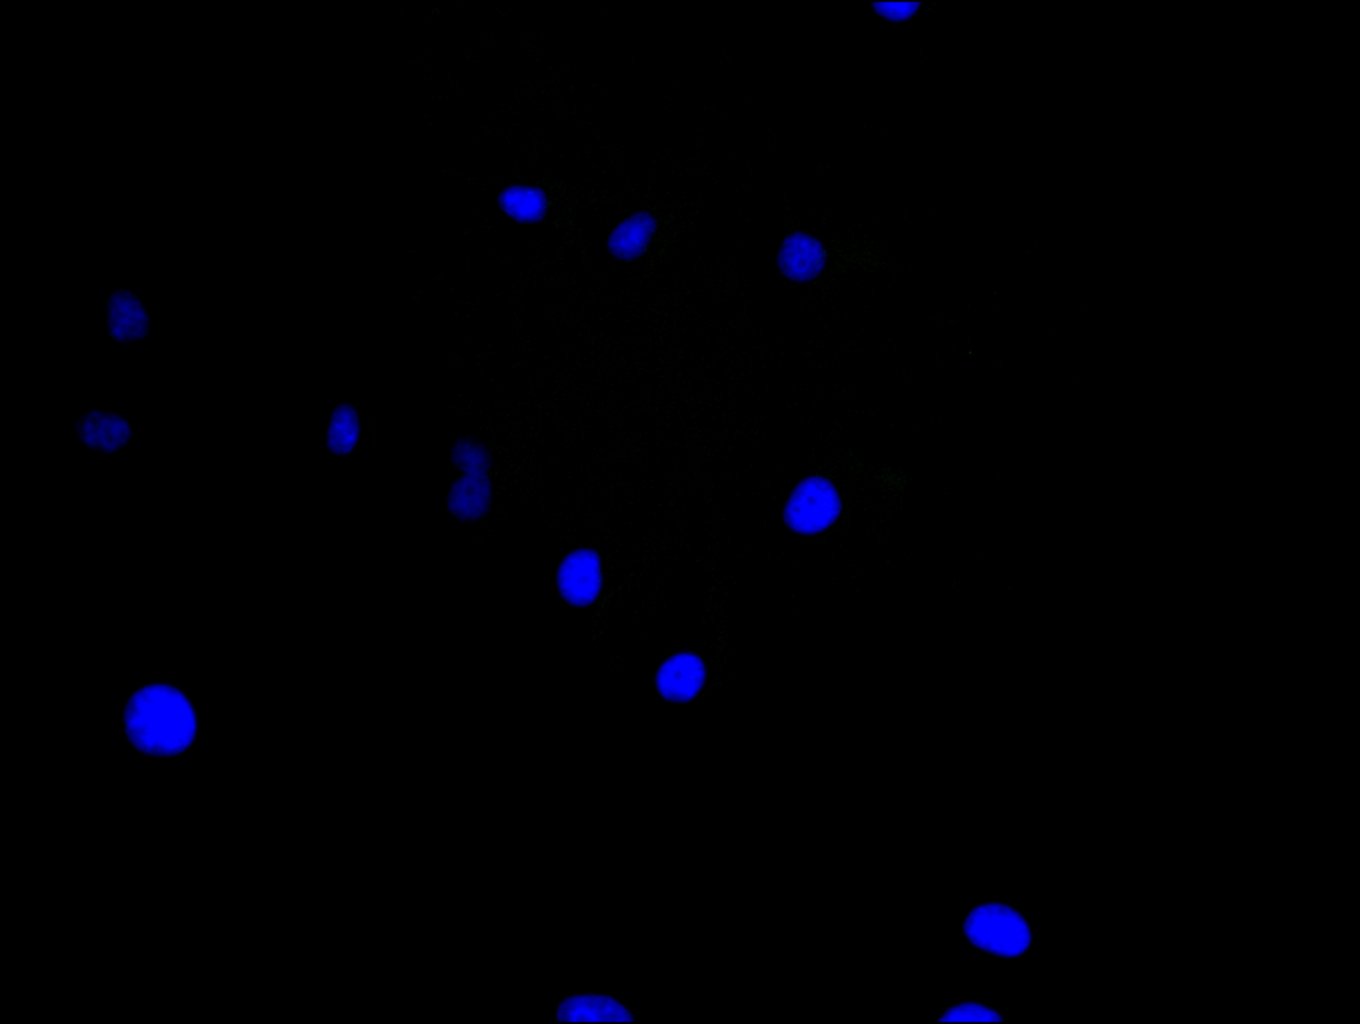

Immunofluorescence staining of Hela cell with CSB-PA009453LA01HU at 1:30, counter-stained with DAPI. The cells were fixed in 4% formaldehyde and blocked in 10% normal Goat Serum. The cells were then incubated with the antibody overnight at 4C. The secondary antibody was Alexa Fluor 488-congugated AffiniPure Goat Anti-Rabbit IgG(H+L).

Immunofluorescence staining of Hela cell with 5% goat serum, counter-stained with DAPI. The cells were fixed in 4% formaldehyde and blocked in 10% normal Goat Serum. The cells were then incubated with the antibody overnight at 4C. The secondary antibody was Alexa Fluor 488-congugated AffiniPure Goat Anti-Rabbit IgG(H+L).